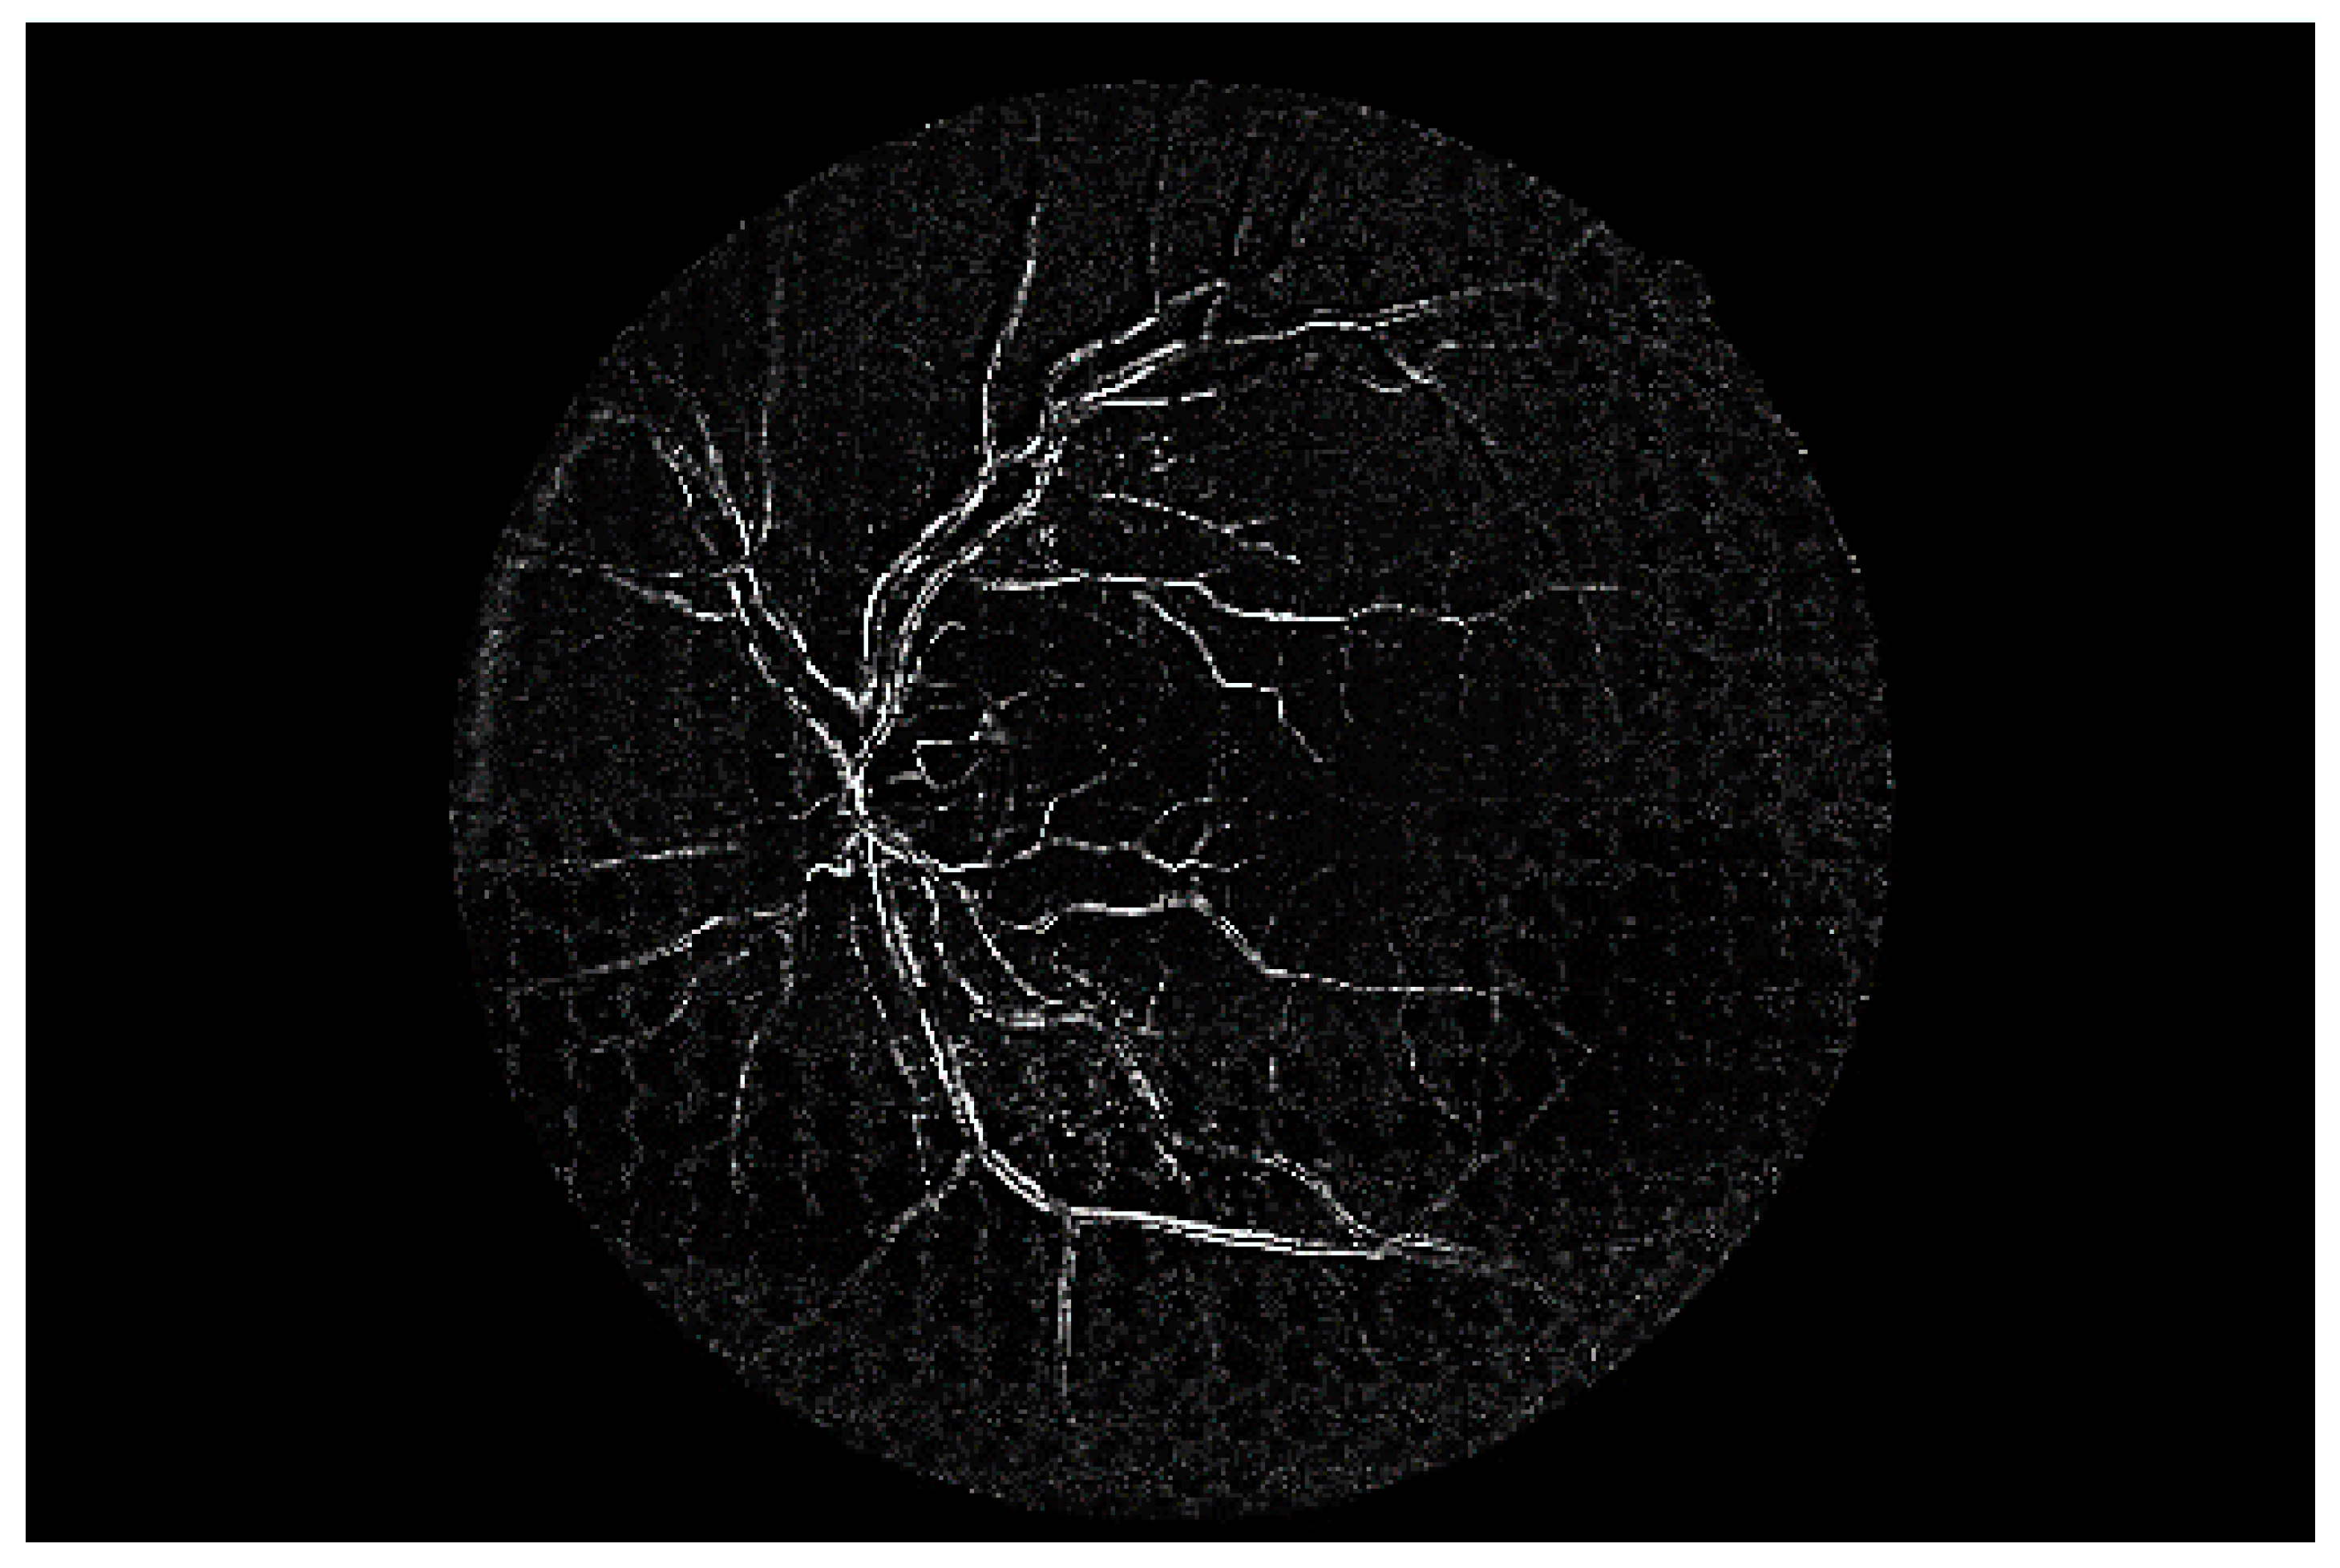

Figure 14 shows a comparison of a vessel image extracted from the original low-quality image with one synthesized by the proposed method. The white noise area at the bottom of the original low-quality image is clearly not present in the synthesized vessel image. As for the bottom part of the vessel stem that was damaged and could not be distinguished, this was created independently with noise removal.

Figure 14. Comparison of low-quality retinal and synthetic vessel images.